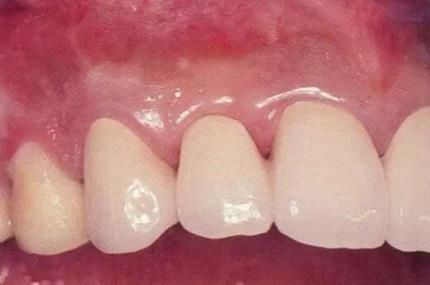

圖16-9    術(shù)后1周。

圖16-10  佩戴最終修復(fù)體時(shí)。